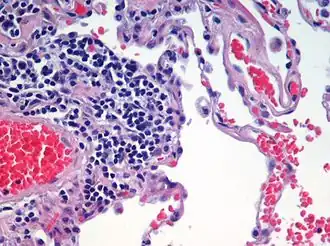

Plicní emfyzém (neboli rozedma plic, latinsky Emphysema pulmonum) znamená trvalé abnormální rozšíření dýchacích cest distálně od terminálních bronchiolů. Je charakterizován úbytkem plicní tkáně.

- Panacinární emfyzém

Postihuje jak bronchiolus tak plicní sklípky. Typicky se vyskytuje u pacientů s chyběním enzymu alfa-1-antitrypsin.